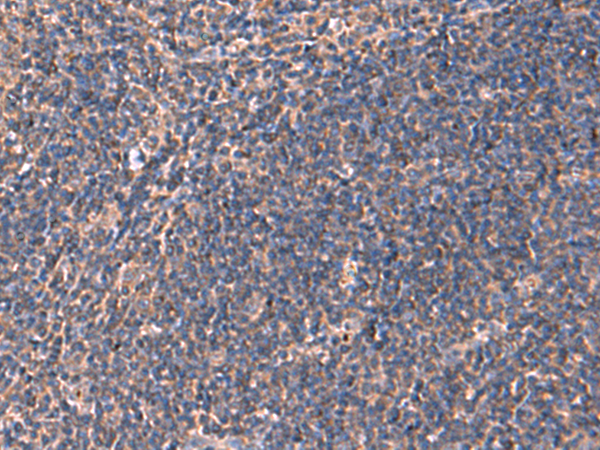

IHC positive control:

Human tonsil and Human cervical cancer

IHC Recommend dilution:

50-300